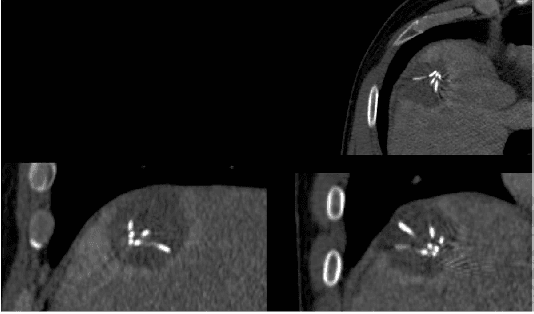

Abstract:Percutaneous radiofrequency ablation (RFA) is a minimally invasive technique that destroys cancer cells by heat. The heat results from focusing energy in the radiofrequency spectrum through a needle. Amongst others, this can enable the treatment of patients who are not eligible for an open surgery. However, the possibility of recurrent liver cancer due to incomplete ablation of the tumor makes post-interventional monitoring via regular follow-up scans mandatory. These scans have to be carefully inspected for any conspicuousness. Within this study, the RF ablation zones from twelve post-interventional CT acquisitions have been segmented semi-automatically to support the visual inspection. An interactive, graph-based contouring approach, which prefers spherically shaped regions, has been applied. For the quantitative and qualitative analysis of the algorithm's results, manual slice-by-slice segmentations produced by clinical experts have been used as the gold standard (which have also been compared among each other). As evaluation metric for the statistical validation, the Dice Similarity Coefficient (DSC) has been calculated. The results show that the proposed tool provides lesion segmentation with sufficient accuracy much faster than manual segmentation. The visual feedback and interactivity make the proposed tool well suitable for the clinical workflow.